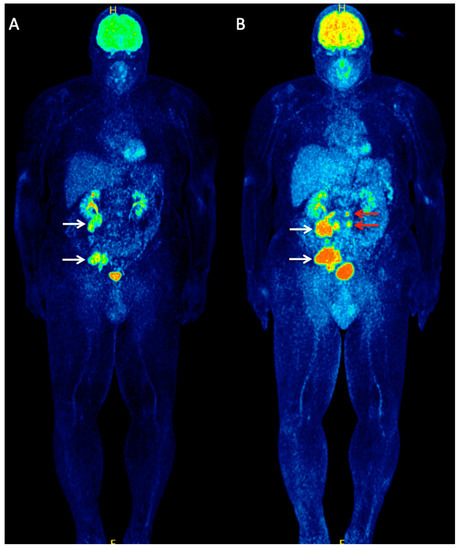

- Taralli, S.; Sollini, M.; Milella, M.; Perotti, G.; Filice, A.; Menga, M.; Versari, A.; Rufini, V. 18F-FDG and 68Ga-somatostatin analogs PET/CT in patients with Merkel cell carcinoma: A comparison study. EJNMMI Res. 2018, 8, 64. [Google Scholar] [CrossRef]

- Epstude, M.; Tornquist, K.; Riklin, C.; Di Lenardo, F.; Winterhalder, R.; Hug, U.; Strobel, K. Comparison of 18F-FDG PET/CT and 68Ga-DOTATATE PET/CT Imaging in Metastasized Merkel Cell Carcinoma. Clin. Nucl. Med. 2013, 38, 283–284. [Google Scholar] [CrossRef]

| Taralli et al. (2018) [35] | Retrospective | 15 (70 years; 80%) | 18F-FDG 68Ga-DOTATOC 68Ga-DOTANOC 68Ga-DOTATATE | On patient-based analysis, 18F-FDG and 68Ga-somatostatin analogs showed both 100% sensitivity, and 85.7% and 71.4% specificity, respectively, without significant difference. On lesion-based analysis, 18F-FDG detected 89% and 68Ga-somatostatin analogs 92% of the lesions, without significant difference. |